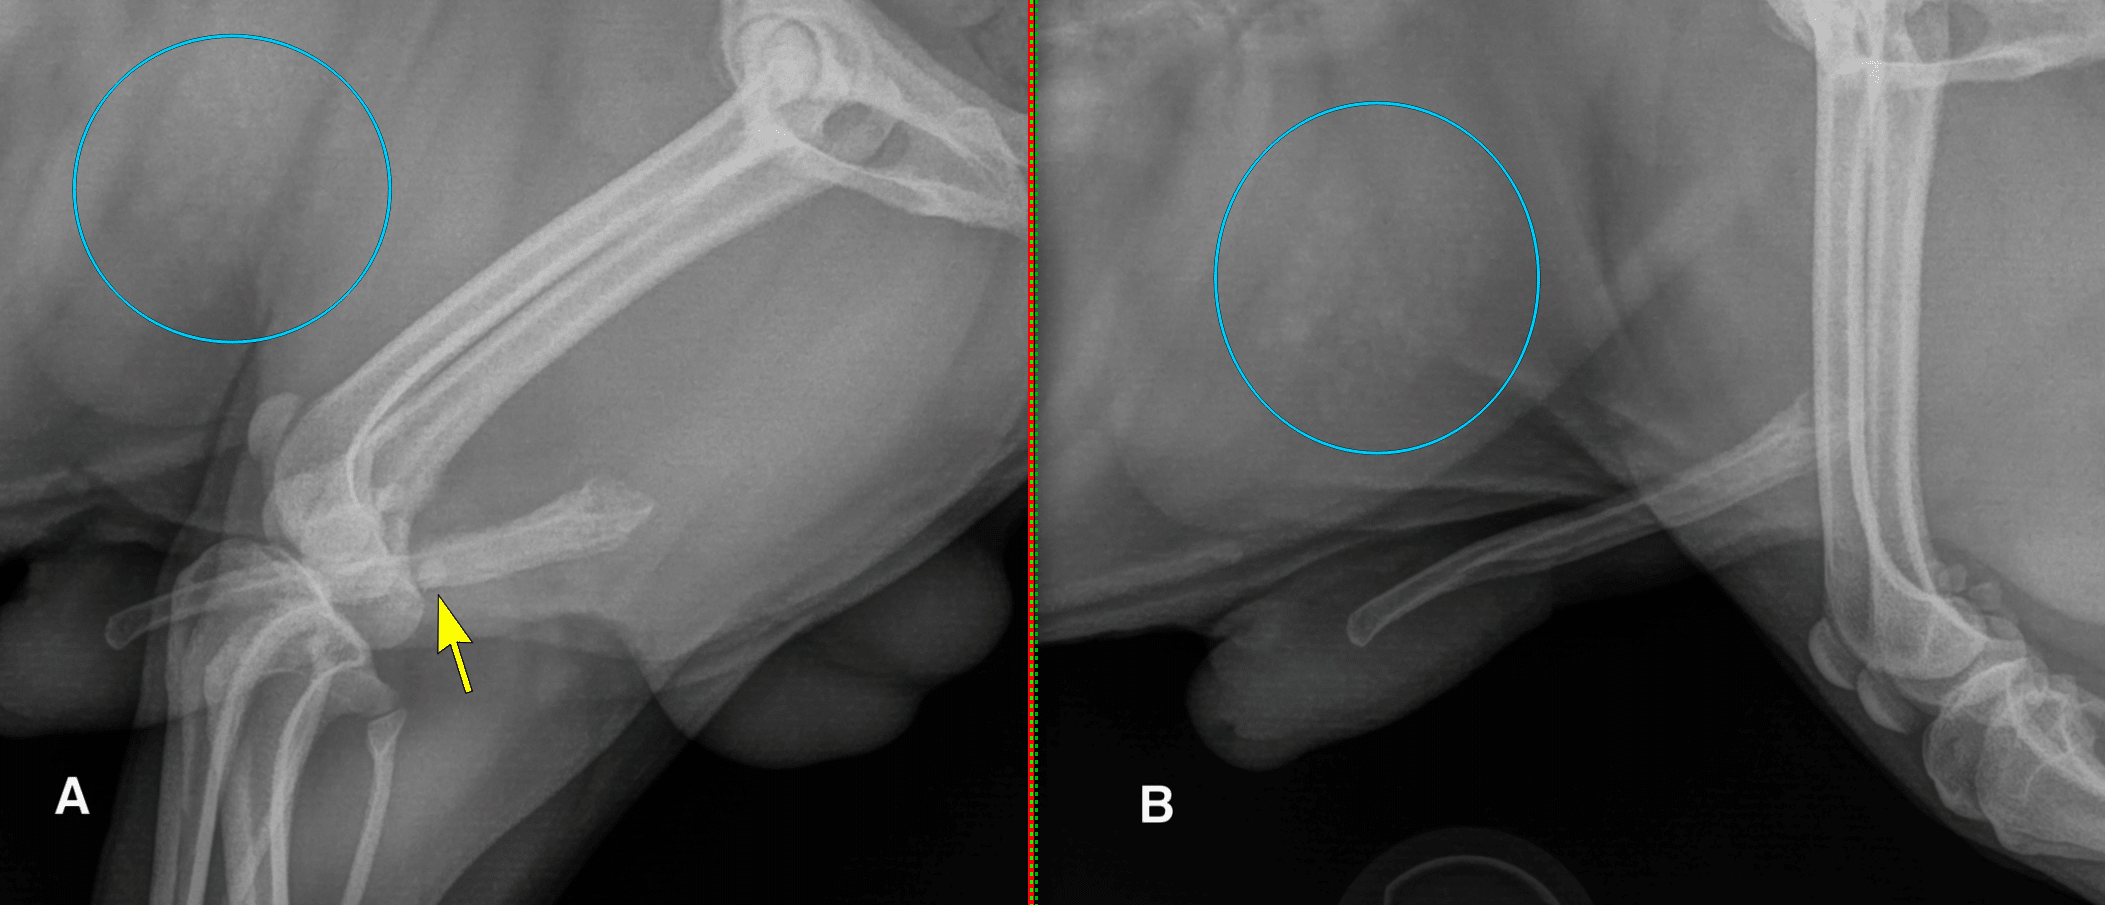

Urethral calculi can be found along any location of the urethra, from the proximal portion cranial to the pubis, to the intrapelvic portion of the urethra, to the more distal part of the urethra caudal to the pelvis in cats and female dogs, and along the entire length of the penile urethra in male dogs. In dogs, it is important not to mistake the ischiatic tuberosities of the pelvis for large urethral calculi on lateral projections (Figure 5). It can also be helpful to obtain a lateral radiograph with one leg raised/abducted to reduce superimposition in the pelvic canal (Figure 6). In male dogs, the most common location for urethral calculi is at the level of the proximal portion of the os penis, as the os penis creates a relative resistance to urine flow. It is usually recommended to obtain lateral views of the penile urethra in male dogs with the pelvic limbs at different degrees of flexion to ensure urethral calculi are not being obscured by the femurs or stifles (Figure 7). Sesamoids in the stifle region (fabellae and popliteal sesamoids) can also be superimposed with the urethra, perfectly mimicking calculi. Having at least two radiographs with the legs in different positions ensures that sesamoids are not misinterpreted as urethral calculi (Figure 8).

Figure 8: Lateral radiographs of a male dog with the pelvic limbs flexed (A) and neutral (B). With the legs bent, the stifles are superimposed with the penis, and a fabella is perfectly positioned to mimic a urolith in the penile urethra (yellow arrow). Note that this patient also has several cystic calculi, some of which are of a similar size and shape to the fabella (blue circles).